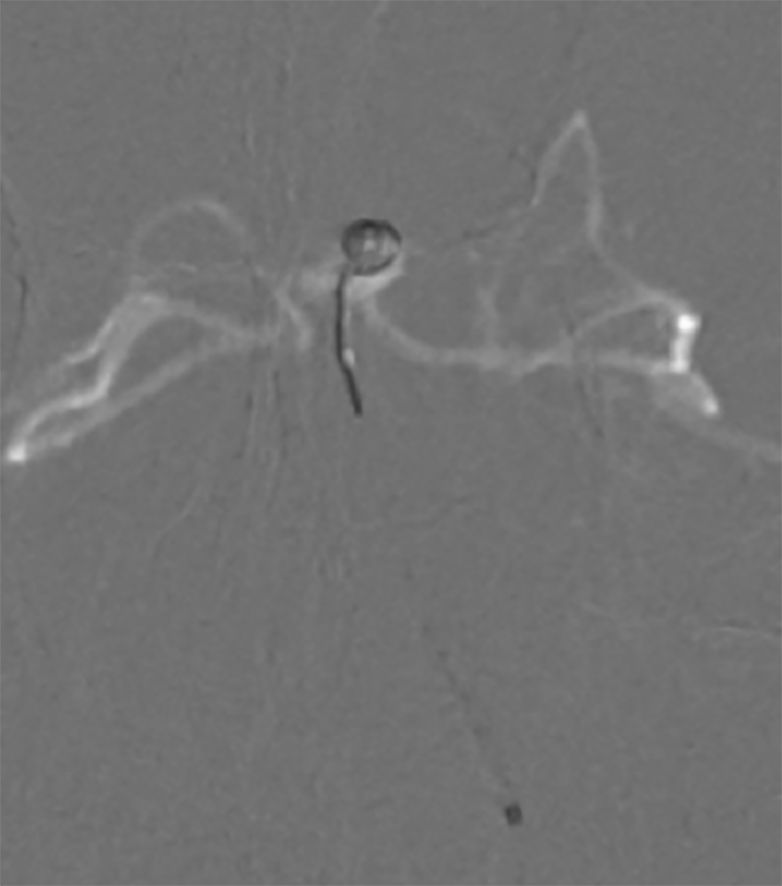

基底动脉进行三维血管重建:基底动脉有较粗和较细的2个管腔,左侧小脑上动脉瘤大小约2.3*2.1 mm(图9)。

图9

进行上述三次微量造影均可见双侧大脑后动脉显影,以及结合基底动脉三维重建图像,故判断基底动脉属于开窗,而非夹层。由于载瘤动脉较细,拟行单微管动脉瘤栓塞术。